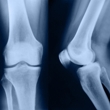

Arthritis

If you feel pain and stiffness in your body or have trouble moving around, you might have arthritis. Most kinds of arthritis cause pain and swelling in your joints. Joints are places where two bones meet, such as your elbow or knee. Over time, a swollen joint can become severely damaged. Some kinds of arthritis can also cause problems in your organs, such as your eyes or skin.